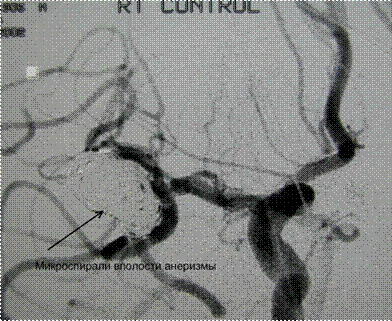

2. Большая аневризма бифуркации Средней мозговой артерии

Большая аневризма с относительно узкой шейкой

Конец процедуры – аневризма полностью закрыта